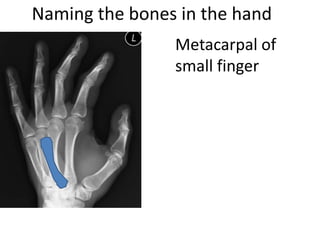

This document provides an overview of hand anatomy including:

- Naming the bones, joints, tendons, nerves and skin landmarks of the hand and wrist.